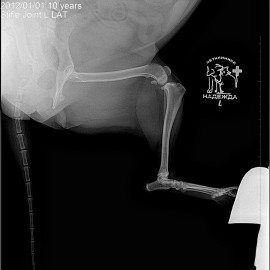

Наш пациент собака по кличке Буся.

Обратились с жалобами на хромоту на левую заднюю лапу.

Были проведены исследования, после которых был поставлен диагноз: разрыв передней крестообразной связки левого коленного сустава. Была проведена операция: TPLO.

Снимки 1-2 до операции.